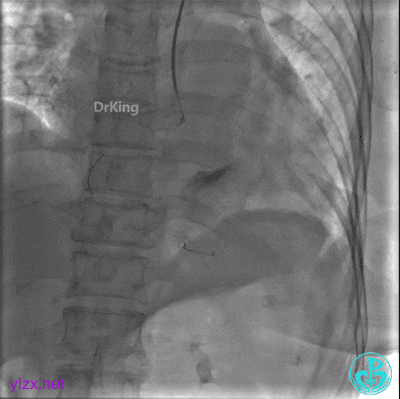

远段造影剂外渗在增加,怎么办?

微导管送入PL分支远段,取明胶海绵颗粒栓塞剂1ml通过微导管向远端血管推注栓塞远端血管。

封堵后造影,PL分支远端血流中断。

心包内无明显积液。